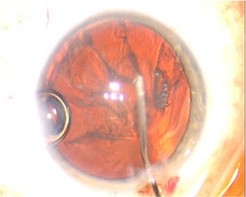

将飞秒激光应用于白内障手术是医生们非常关心的话题。飞秒激光辅助白内障超声乳化手术,是利用飞秒激光代替医生划开切口,并预先分割患者眼睛囊膜内的浑浊晶体,整个过程都有电脑扫描成像技术辅助,医生再用超声波去除晶体。该手术的伤口复原时间虽与超声乳化手术相同,但患者更快恢复视力。

环形前囊膜切口→激光切割碎核→角膜切口

4、激光粉碎晶体核